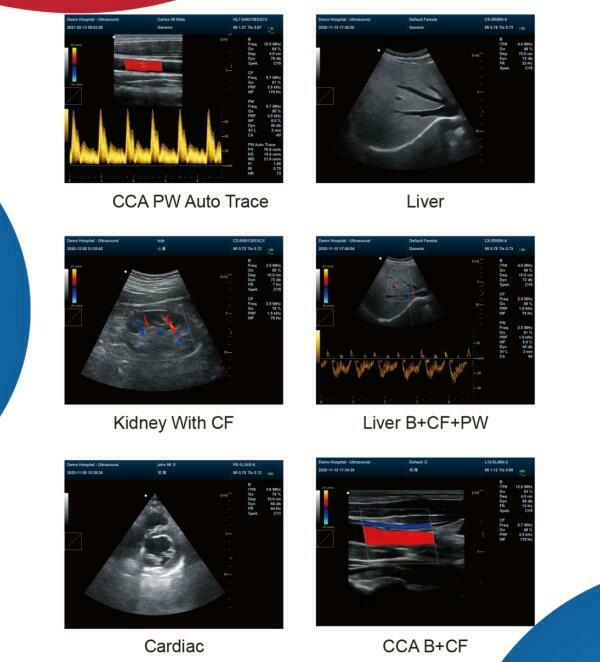

Additionally, the device includes Power Doppler functionality, which enhances the ability to detect blood flow and other internal processes. This technology provides more detailed imaging, allowing for better patient assessment and treatment planning. The Doppler ultrasound functionality ensures that even the smallest anomalies can be detected with clarity and precision.

The user interface of the Laptop Color Doppler Ultrasound is designed for ease of use. It features a high-resolution display, intuitive controls, and customizable settings. This makes it accessible for both new and experienced Sonographers. The device runs on powerful software that supports various diagnostic applications, ensuring versatility in its use. Therefore, it can be used for a wide range of procedures, from obstetric exams to cardiac assessments.

For educational purposes, the imaging capabilities of this machine are excellent. High-quality visuals aid in the training of new medical personnel, providing clear examples of various medical conditions. This makes the Laptop Color Doppler Ultrasound a valuable asset not just for patient care, but also for medical education and research.